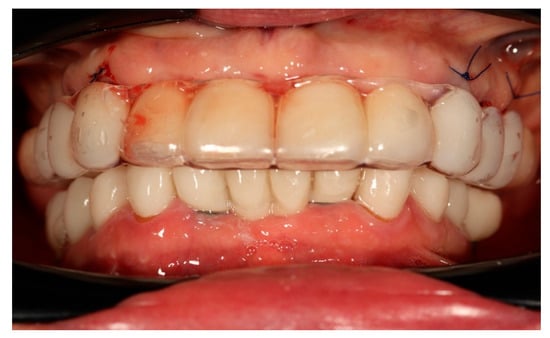

Finally, the prosthesis was delivered by fixing to the multi-unit abutments with screws. Clinical adjustments were performed to ensure perfect fit, occlusion, phonetics, and aesthetics. The patient reported immediate improvement in comfort and satisfaction compared to the acrylic splint (Figure 9 and Figure 10).

Figure 9. Digitally planned, 3D-printed full-arch provisional restoration delivered early and fixed to the multi-unit abutments with screws, shown in situ (occlusal view).